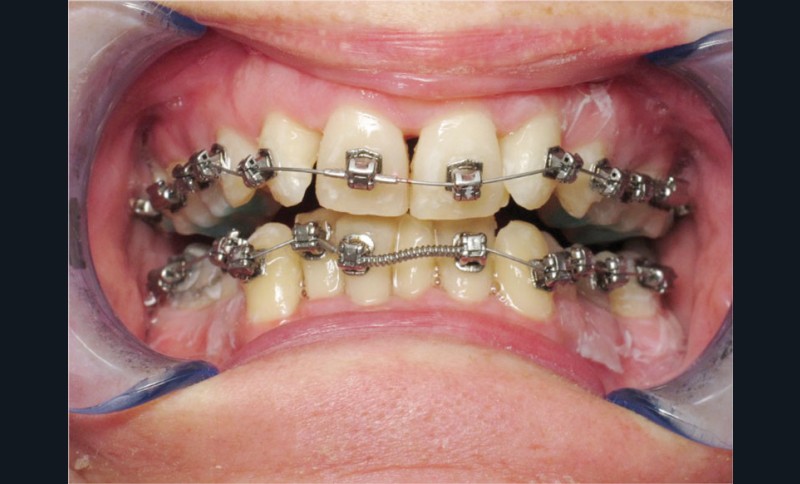

Un appareillage Damon métal a été mis en place, réalisé à partir d’un set up numérique Insignia pour obtenir un contrôle précis des torques et de la forme d’arcade et réduire le temps de finition grâce à un collage indirect très précis.

De larges surélévations postérieures étalées ont été mises en place et la patiente a porté des élastiques précoces suivant les principes de la technique Damon. Les 14 et 24 rempliront le rôle des 13 et 23.

Conclusion

Les objectifs de traitement ont été remplis. Nous avons observé un excellent contrôle du torque et une absence de perte de l’occlusion postérieure grâce à la technique Insignia.